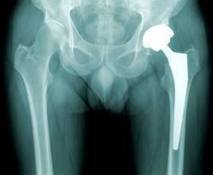

PARIS, 7 sept 2012 (AFP) - Le patient ne peut pas demander des indemnités au médecin qui aurait posé une prothèse défectueuse, à moins que ce médecin n'en soit lui-même le producteur.

L'obligation de sécurité qui pèse sur un médecin concerne les soins, traitements et techniques qu'il doit dispenser, explique la Cour de cassation, mais non sur les produits qu'il utilise.

Pour les juges, les prestataires de services de soins ne peuvent être assimilés à des distributeurs de produits ou dispositifs médicaux. Il est donc exclu que l'éclatement anormal d'une prothèse en silicone puisse être reproché au chirurgien qui l'a posée.

Le procès doit être fait au producteur de la prothèse, lequel est responsable du défaut de son produit. La justice se fonde sur une directive européenne de 1985 qui prévoit cependant que le médecin puisse être visé si le producteur n'est pas identifié. En pareil cas, selon la directive, le médecin sera alors considéré comme producteur.

Un médecin n'a donc pas d'obligation de sécurité "de résultat" quant à la qualité de ce qu'il utilise. Il n'est responsable de la défectuosité de la prothèse que si elle est liée à une faute lors de l'opération.